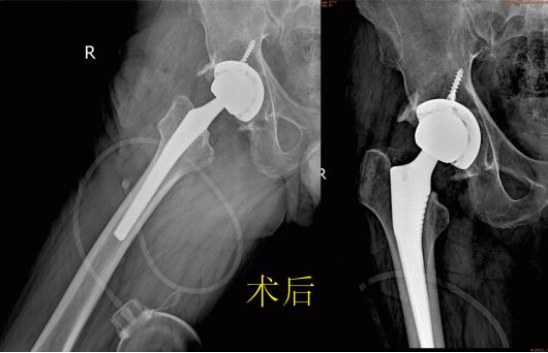

通过与医生沟通后很快办理了住院手续。骨科接诊医生仔细进行体格检查,完成系统的辅助检查后,全科就患者病情进行讨论决定最终的手术方案为:人工全髋关节置换术。在手术室及麻醉师的协助下,手术顺利的完成。术后第3天患者就可以下地扶助行器行走良好,患者及家属均表示很满意。 九江市第一人民医院开发区分院/朱挺平